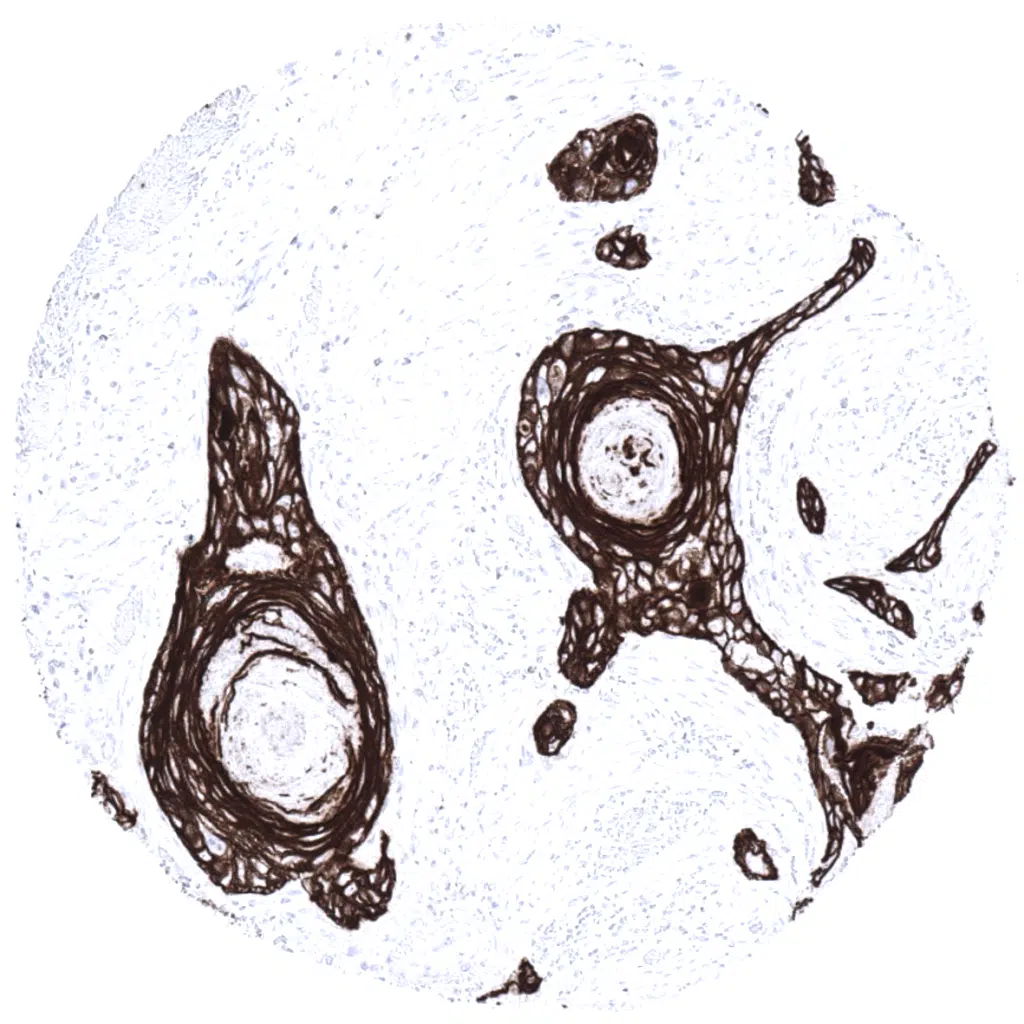

Cervical squamous cell carcinoma with strong Cytokeratin 5 immunostaining.

Squamous cell carcinoma of the uterine cervix showing strong Cytokeratin 5 immunostaining.